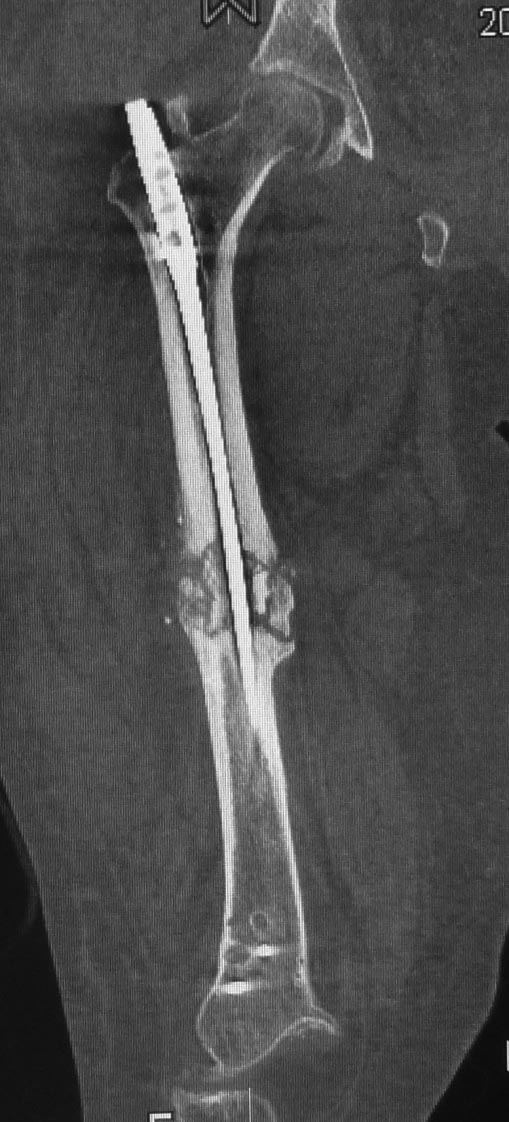

Уважаемые коллеги. Хотелось бы выслушать мнения и советы по представленному случаю. Пациент 42 лет, вес 130 кг, рост около 160 см, сахарный диабет в легкой форме (впервые выявлен после травмы). Травма в феврале 2011 г. - упал с мотоцикла на отдыхе за рубежом. По возвращении в Россию был прооперирован в несколько этапов: в марте 2011 г. - остеосинтез обеих костей правого предплечья пластинами по поводу открытого перелома; интрамедуллярный остеосинтез правого бедра; остеосинтез проксимального конца правой большеберцовой кости. В апреле 2011 г. был доставлен 1 блокирующий винт в дистальное отверстие гвоздя и выполнена пластика крестообразных и наружной боковой связок левого коленного сустава. В феврале 2012 г. были удалены фиксаторы с проксимального конца правой большеберцовой кости и выполнена пластика крестообразных и наружной боковой связок правого коленного сустава. За это время пациент смог начать ходить, сначала с костылями, а затем - без дополнительной опоры. Летом 2013 г. решил укрепить ноги с помощью подъемов пешком на пятый этаж. В результате - усталостная рефрактура правого бедра и перелом интрамедуллярного гвоздя. 09.09.2013 - реостеосинтез латеральным бедренным гвоздем с пластикой костной аутостружкой + СhronoS. Сейчас, через 6 мес после операции, может ходить без дополнительной опоры, периодически беспокоит болезненность в области правого бедра. На сегодняшних КТ - отсутствие признаков консолидации. Нужно ли что то делать и, если да, то что? Рассматриваемые варианты: повторная костная пластика дефекта; доставить блокирующие винты (самый проксимальный винт был удален через 3 мес после операции). Еще раз менять гвоздь не хотелось бы. На представленных снимках: бедро в 2011 г., через несколько мес после операции; в 2012 г., на стадии консолидации; со сломанным гвоздем; сразу после повторной операции (3 рентгенограммы). Все КТ - сегодняшние. Заранее спасибо за ответы.

Источник проблем - отсуствие рассверливания, тонкий гвоздь и костная пластика. При интрамедуллярном остеосинтезе (относительная стабильность) класть кусочки кости открыто бесполезно - не приживут. Только еще ухудшили кровоснабжение концов. А что там с длиной сегмента? Если длина не потерялась - реостеосинтез с рассверливанием, как А.Семенистый написал. Если укорочение - удалить, остеотомия на другом уровне и дистракиця, на стыке - компрессия, и по достижении нужной длины - заштифтовать с рассверливанием, аппарат снять только после запирания гвоздя.

Костная пластика делалась стружкой из фрагментов большого вертела: верхний конец предыдущего гвоздя был погружен в него на пару см (первый гвоздь ставился не у нас, я только доставил второй дистальный блокирующий винт)и гранулами СhronОs. Учитывая совершенно необъятные размеры бедра, удаление сломанного гвоздя получилось достаточно травматичным. Пришлось широко открываться проксимально, на уровне перелома и дистальнее, чтобы сформировать окошко для выбивания дистального отломка гвоздя (дистальный конец гвоздя не имел отверстия). После операции около месяца собиралась жидкость в области большого вертела (серома), на фоне пункций постепенно ушла. Поэтому и хотелось бы избежать еще одного вмешательства на уровне большого вертела.